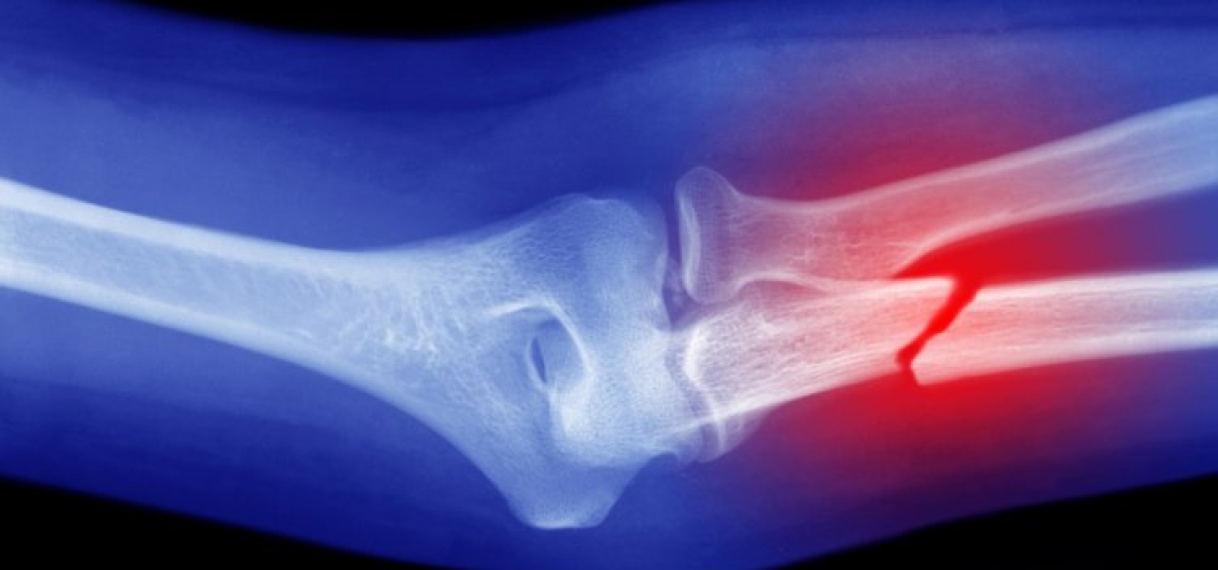

Chinese onderzoekers beweren een revolutionaire ‘superlijm’ voor botten te hebben ontwikkeld. Met de bottenlijm kunnen breuken, die normaal gesproken maanden nodig hebben om te genezen, binnen enkele minuten worden hersteld.

Volgens Lin Xianfeng, orthopedisch chirurg en hoofd van het onderzoeksteam, wordt de lijm in de botten aangebracht door middel van een enkele injectie, zo meldt The Global Times. De wonderlijm met de naam ‘Bone-02’ lijmt dan ‘de gebroken botfragmenten in slechts 3 minuten aan elkaar’, aldus de chirurg.

Volgens het onderzoeksteam zijn metalen platen om botten aan elkaar vast te zetten in de toekomst verleden tijd. De lijm zou een maximale hechtkracht hebben van 180 kilo. Een ander kenmerk van ‘Bone-02’ is dat het volgens de onderzoekers op natuurlijke wijze door het lichaam kan worden opgenomen. Dit, tijdens het genezingsproces van het bot. Een operatie om lijmresten te verwijderen is daardoor niet nodig.